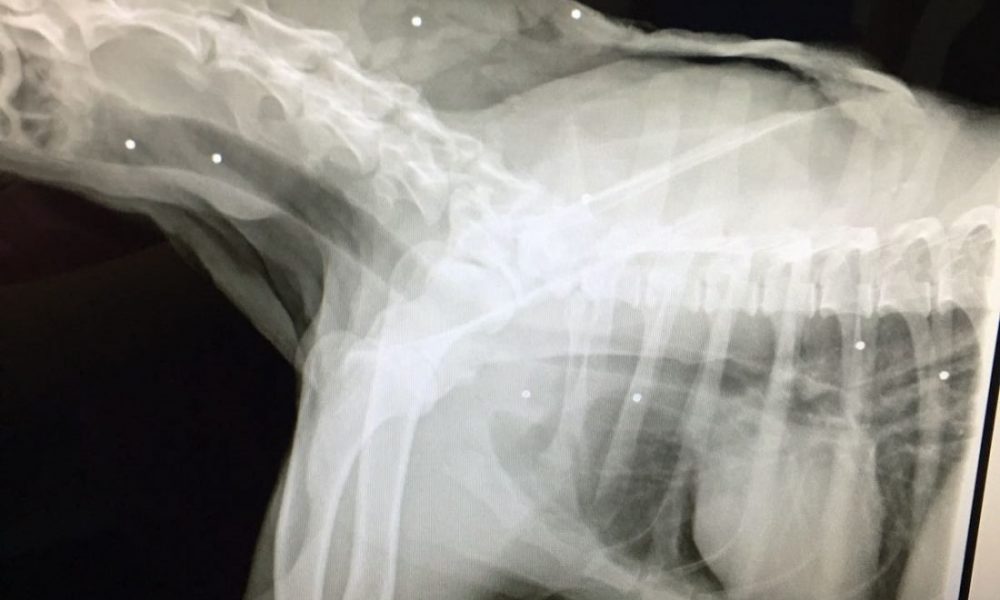

La Guardia Civil ha abierto una investigación para aclarar las circunstancias de la muerte de un perro mestizo de 7 años que la pasada semana sufrió...